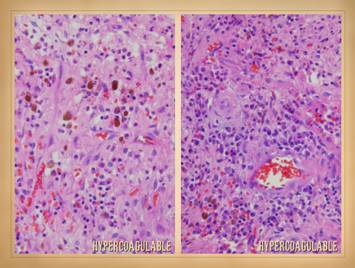

19

Like anything else in medicine, proper diagnosis of a wound or underlying disease starts with a history and physical exam, formulation of a differential diagnosis if the exact diagnosis is not yet evident, then resolution of the diagnosis by further testing.  History was covered on the preceding slide.  This slide concerns what is apt to be found on examination, both the initial physical plus subsequent observations as treatment is managed.

Hypercoagulable ulcers have features predominantly attributable to ischemia and arterial insufficiency.  To the extent that they might have an associated immune component, there may be inflammatory changes along with ischemic changes.  However, for prototypical coagulopathic ulceration, the pattern is one of thrombo-infarction rather than inflammation-lysis.  This means that they have no unique nor pathognomonic features, but they do have an eminently distinctive appearance.

Features of gross appearance include:  ischemic infarction (black desiccated eschar), periwound vascular stasis (cyanotic plethora as opposed to the scarlet hyperemia of inflammation), active ulceration (observable at the margins where skin is dying, until the cause of ischemia has been corrected), absence of edema, absence of gross inflammation, and a weak or absent wound module.  Unlike with classic arterial diseases, patients will have these signs of arterial ischemia while still having good pulses.  If a patient has a related condition, such as secondary venous disease caused by the chronic hypercoagulopathy, then exam can be mixed with signs of the multiple problems.  However, for paradigm hypercoagulable ulceration, the picture is one of localized arterial ischemia in the face of good pulses.

Observations over time and care, until definitive treatment is rendered, can be summed up simply as “impaired wound behavior characteristic of severe ischemia “.  Wound behavior is continuously pathological, with persistent active necrosis, pathergy, and active ulceration.  The wounds are recalcitrant, with impaired dynamics and failure to make meaningful progress until ischemic conditions are relieved.  Repetitive occult micro-thrombotic events result in rapid evolution and slow resolution of the ulcers.  If wrong therapies are attempted based on wrong diagnosis, if no precautions are taken to prevent or mitigate thrombosis and ischemia, then no results or contrary results will happen.  This is especially problematic for attempted surgery which will fail due to pathergy, necrosis, and dehiscence.

Left upper:  multifocal ankle infarcts in a patient with protein C and anticardiolipin abnormalities.  Note the black eschar, absence of lytic ulceration and tissue dissolution, and absence of generalized edema and panniculitis beyond the immediate zone of the skin infarcts.   Left center:  distal leg ulcers in a patient with good ankle pulses and anti-thrombin-3 deficiency.  Note dry black skin infarcts and eschar, vascular stasis and cyanosis, absence of edema, in fact with wrinkles due to desiccation, all consistent with severe micro-occlusive ischemia.  Left lower:  wound infarcts with acute black eschar, in a forearm wound, in a patient with rheumatoid and proteins C & S abnormalities.  Right:  ulceration of the ankle after biopsy of a small lesion, in a patient with protein C deficiency and positive cryoglobulins.  Note absence of generalized edema and inflammation, a caput medusa or venous “spider” consistent with prior thrombosis and valvular reflux, and the histologic findings of thrombosis and vascular necrosis.